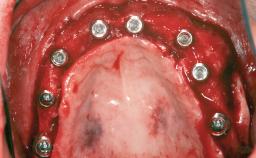

A 20-year-old woman was referred for implant therapy in 2004. Her medical history revealed no significant findings, and neither did she smoke nor take any medications. An extraoral examination revealed no abnormalities of the skin, hair or nails. The intraoral examination revealed only 11 permanent teeth clinically. These were normal in shape, size, and color. In addition, eight retained deciduous teeth (53, 62, 63, 71, 72, 73, 81, 82) were present. No abnormalities were detected during the general examination. The family history revealed that the patient’s father and two sisters were on record with similar conditions. The clinical examination revealed a thick gingival biotype. No recession of the attached gingiva was noted, but the retained deciduous teeth were mobile and unsightly. As a syndrome had not been diagnosed, the case was categorized as non-syndromic oligodontia.

# of Implants 12

Type of Implants One-Piece|Reduced-Diameter

Bone Augmentation Horizontal|Staged

Augmentation Materials Autogenous chips|Autogenous block(s)|Membrane